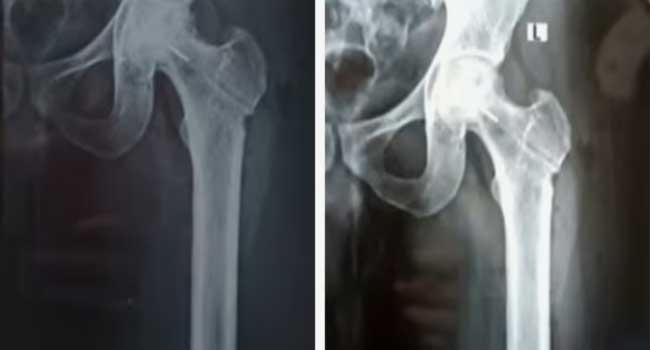

തിരുവനന്തപുരം: തിരുവനന്തപുരം ജൂബിലി മെമ്മോറിയൽ ആശുപത്രിക്കെതിരെ ഗുരുതര ചികിത്സാപിഴവ് പരാതി. ഇടുപ്പ് എല്ലിൽ ശസ്ത്രക്രിയ ചെയ്യുന്നതിനിടെയാണ് സംഭവം. രക്തയോട്ടം കൂട്ടാനുള്ള ശസ്ത്രക്രിയക്കിടെ ഡ്രിൽ ബിറ്റ് ഒടിഞ്ഞു കയറുകയായിരുന്നു. ശസ്ത്രക്രിയയ്ക്കിടെ മലയിൻകീഴ് സ്വദേശി ജിജിൻ ജോസിൻെറ ഇടത് ഇടുപ്പ് എല്ലിലാണ് ഡ്രിൽ ബിറ്റ് ഒടിഞ്ഞു കയറിയത്. ജിജിൻെറ പരാതിയിൽ കൻോൺമെന്റ് പോലീസ് കേസെടുത്തു. അതേസമയം ലോഹ കഷണം ഇനി നീക്കം ചെയ്യാനാകില്ലെന്നും അതു ഇരിക്കുന്നതിനാൽ പ്രശ്നങ്ങളുണ്ടാകില്ലെന്നും രോഗിയെ അറിയിച്ചതായി ആശുപത്രി അധികൃതർ വിശദീകരിക്കുന്നു. കൊല്ലം ജില്ലാ ആശുപത്രിയിൽ അടിയന്തര […]